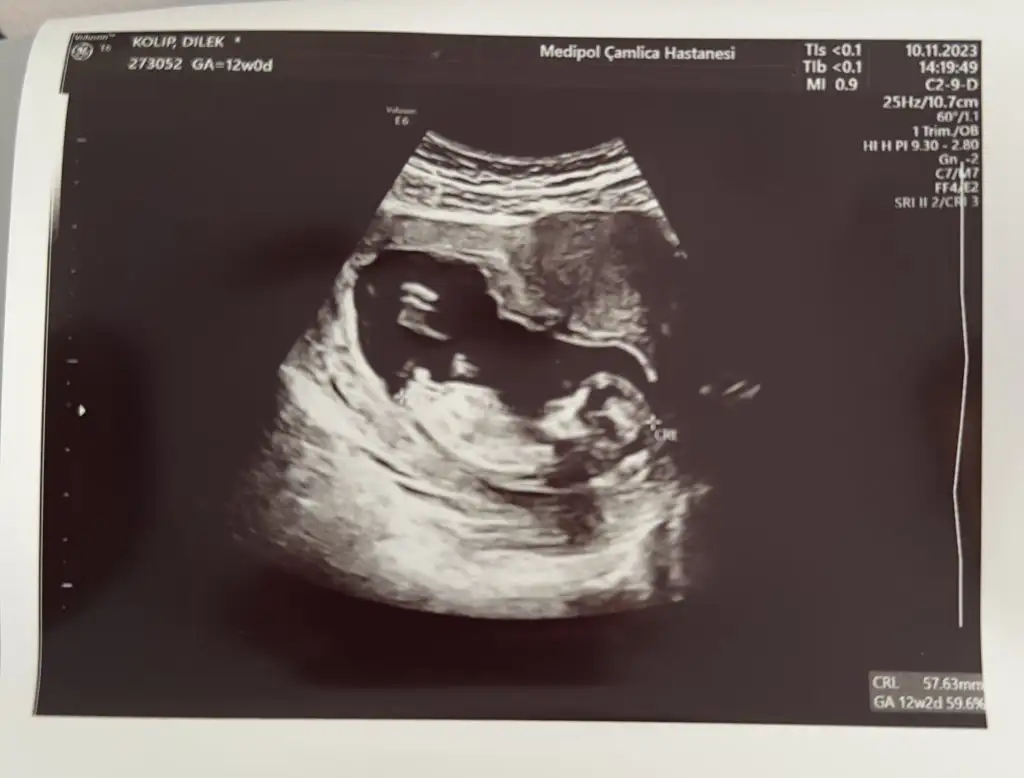

12 haftalık bende çok kerak ediyorum yorumlar mısınızz🥰

Sırayla 8-12-14 hafta hepsi karından yorumlarsanız sevinirim

12 haftalıkken erkege benziyor denildi 14 hafta kıza benziyor denildi 15 haftalık oldum hala bilmiyorum bebisimin cinsiyetini dahada doktora gitmeme 3 hafta var meraktan çatlamak üzereyim 😅